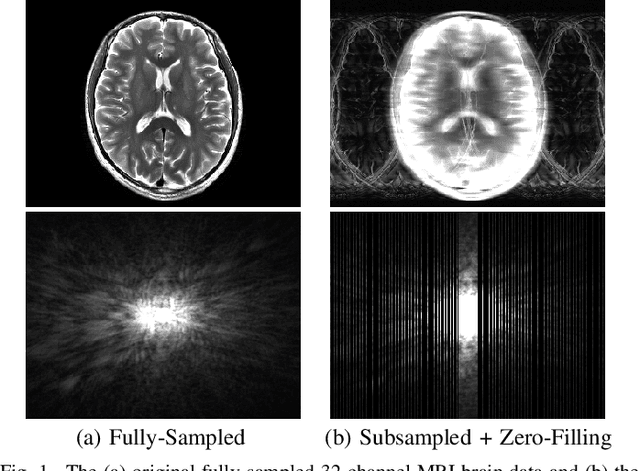

Abstract:Ill-posed linear inverse problems appear frequently in various signal processing applications. It can be very useful to have theoretical characterizations that quantify the level of ill-posedness for a given inverse problem and the degree of ambiguity that may exist about its solution. Traditional measures of ill-posedness, such as the condition number of a matrix, provide characterizations that are global in nature. While such characterizations can be powerful, they can also fail to provide full insight into situations where certain entries of the solution vector are more or less ambiguous than others. In this work, we derive novel theoretical lower- and upper-bounds that apply to individual entries of the solution vector, and are valid for all potential solution vectors that are nearly data-consistent. These bounds are agnostic to the noise statistics and the specific method used to solve the inverse problem, and are also shown to be tight. In addition, our results also lead us to introduce an entrywise version of the traditional condition number, which provides a substantially more nuanced characterization of scenarios where certain elements of the solution vector are less sensitive to perturbations than others. Our results are illustrated in an application to magnetic resonance imaging reconstruction, and we include discussions of practical computation methods for large-scale inverse problems, connections between our new theory and the traditional Cram\'{e}r-Rao bound under statistical modeling assumptions, and potential extensions to cases involving constraints beyond just data-consistency.